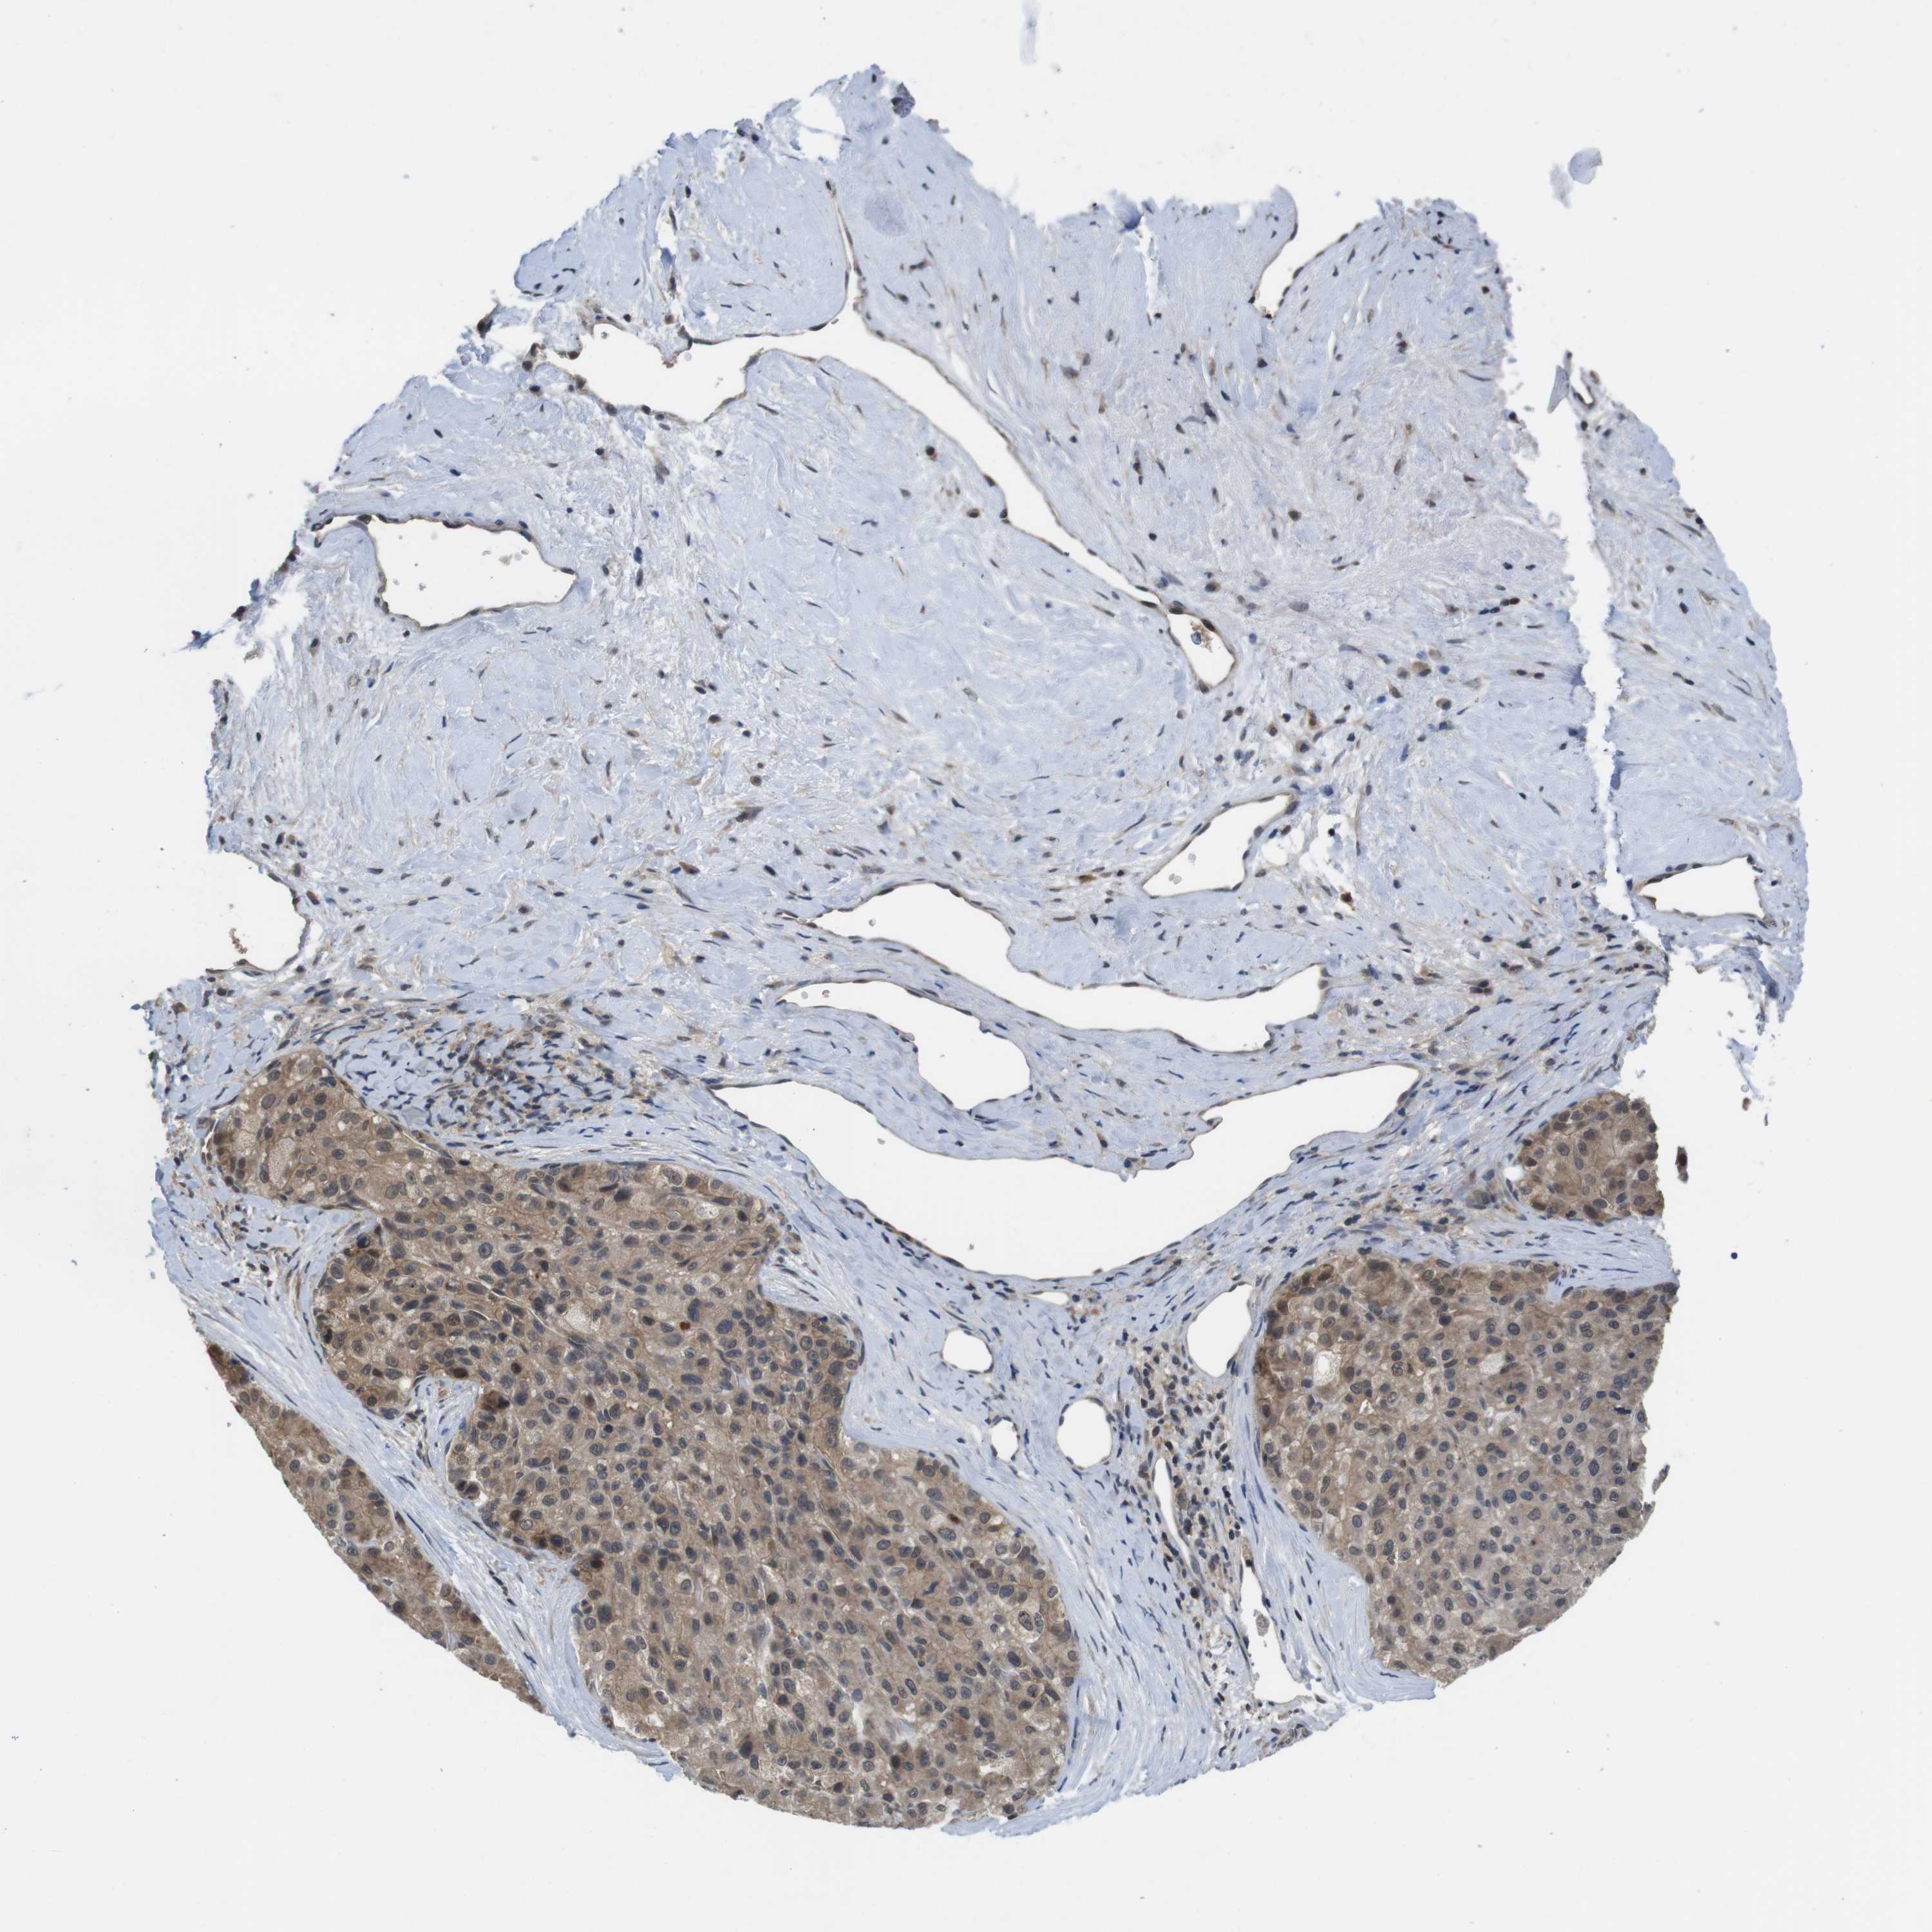

LIVER CANCER - Protein expressioni

A mouse-over function shows sample information and annotation data. Click on an image to view it in a full screen mode. Samples can be filtered based on level of antibody staining by selecting one or several of the following categories: high, medium, low and not detected. The assay and annotation is described here.

Antibody stainingi

Antibody staining in the annotated cell types in the current human tissue is reported as not detected, low, medium, or high, based on conventional immunohistochemistry profiling in selected tissues. This score is based on the combination of the staining intensity and fraction of stained cells.

Each image is clickable and will lead to virtual microscopy that enables deeper exploration of all samples and also displays staining intensity scores, fraction scores and subcellular localization as well as patient and tissue information for each sample.

Antibody CAB010209

Cholangiocarcinoma

Carcinoma, Hepatocellular, NOS